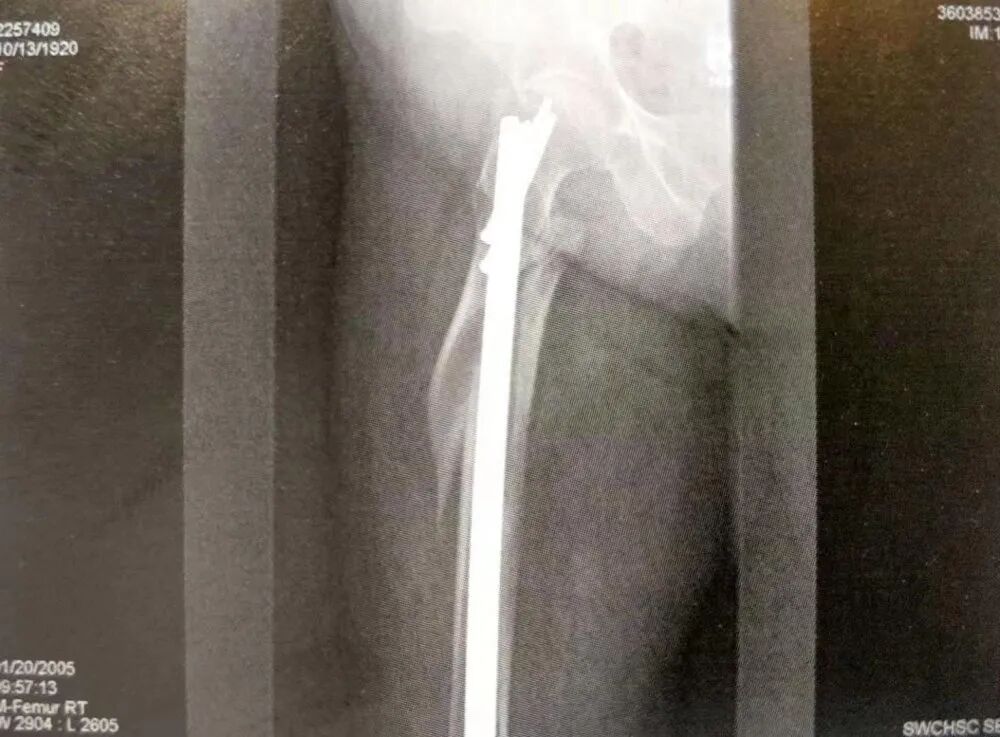

3)复杂的股骨上段骨折累及到转子下

▲ 复杂的股骨上段骨折累及到转子下